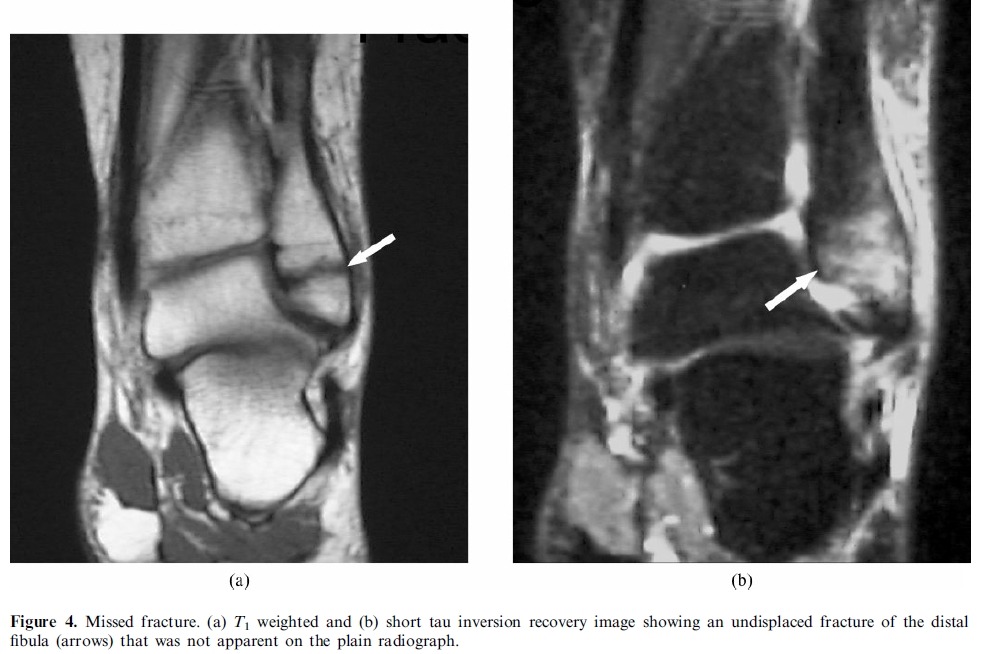

# MRI is the most suitable technique for global assessment of bone and soft tissues for persistent pain following injury.